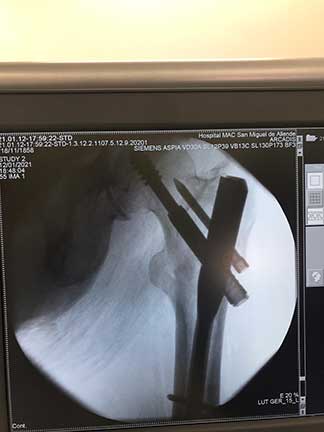

Fractura

de cadera

Es la pérdida de la continuidad del tejido óseo en la articulación de la cadera, producidas por caídas o traumatismos de alta energía, la cual se caracteriza por dolor intenso, incapacidad funcional, chasquidos, acortamiento y rotación de la pierna, el diagnóstico definitivo es por radiografía o tomografía.

¿Por qué se realiza?

El tratamiento en pacientes adultos regularmente es quirúrgico, el cual se realiza con implantes de metal que recuperan la anatomía normal de la articulación similar a la previa fractura, los cuales pueden ser clavos, placas, tornillos o prótesis.